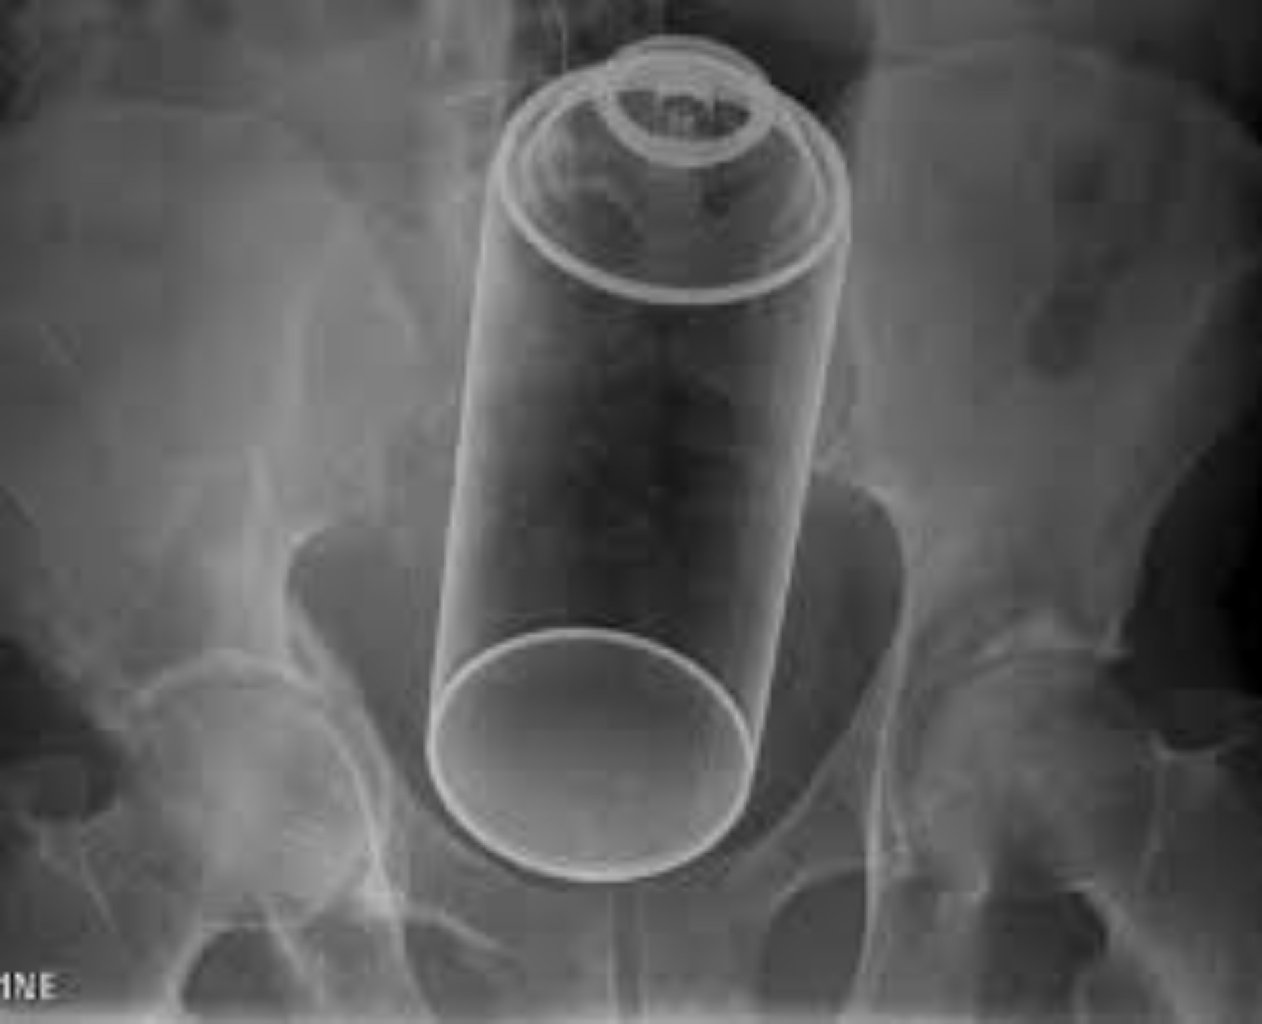

Düz bağırsaqlarda yad cisimlərin aşkar edildiyi hallarda, bu obyektin bağırsaqlara necə və nə vaxt d ...